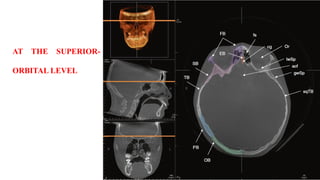

NORMALANATOMICAL LANDMARKS

AT THE SUPRA-

ORBITAL LEVEL

AT THE SUPERIOR-